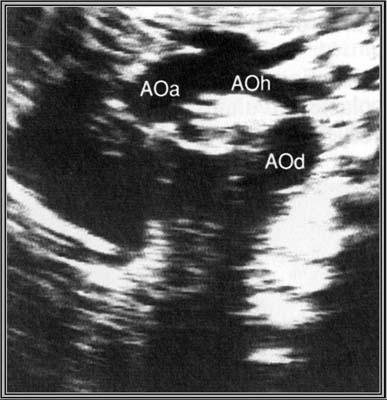

Diagnostic anténatal difficile même en incidence de la crosse de l’aorte.

Elles siègent presque toute au niveau de l’isthme aortique entre l’artère sous-clavière gauche et le canal artériel (alors que les coarctations du grand enfants sont post-ductales).

Soit strictement localisée à l’isthme aortique, soit associée à une hypoplasie plus ou moins longue de la crosse de l’aorte.

Signes indirects :

- Crosse de l’aorte de plus en plus hypoplasique avec la grossesse

- Dilatation et hypertrophie du VD

- Inégalité du calibre de l’aorte par rapport à celui de l’AP (AP>Ao)

Forme extrême : Interruption de la crosse de l’aorte.

- Hypoplasie aorte ascendante et anneau aortique